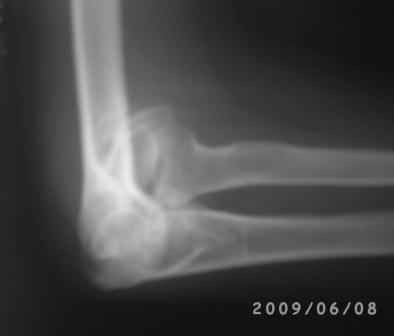

Уважаемые коллеги! Обратился больной 17 лет с жалобами на деформацию пр. локтевого сустава.

Травму получил 7 лет назад. Локально: вальгусная деформация л/с под углом 45гр., сгибание -30, разгибание-170гр., наружный мышелок плеча под пальцами подвижен, что интересно- мышелок плеча при пронации и супинации п/плечья вместе с головкой луча поднимается и опускается( см снимки).